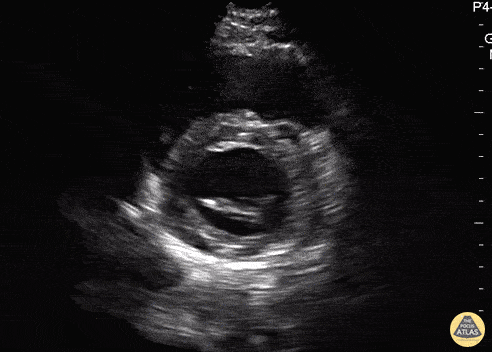

Normal Cardiac Anatomy - Parasternal Short Axis (Mitral Valve) - Normal

In this view we are evaluating the heart in cross-section. In the center of the screen is the muscular walled left ventricle, which should form a perfect circle. At the beginning of the clip, we see the “fish mouth” appearance of the mitral valve as it opens and closes. Then the probe is tilted inferiorly towards the apex and the papillary muscles come into view. The smaller, thin walled, crescent shaped right ventricle is seen superficially and to the left of the screen. Hannah Kopinski - MS4, Dr. Lindsay Davis - NYU/Bellevue Department of Emergency Ultrasound, Dr. Matthew Riscinti - Kings County Emergency Medicine